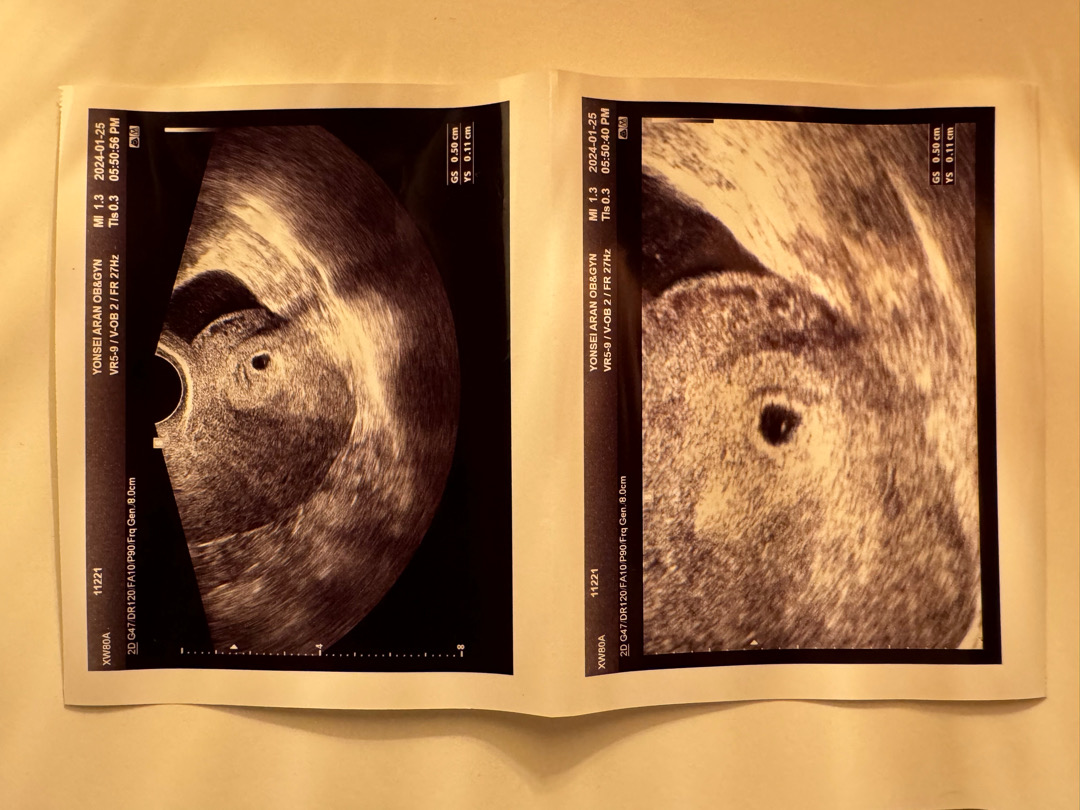

4주6일 초음파

병원 천천히 가야지 했는데 불안해서 못참고 오늘 병원 다녀왔어여 😅 4주6일 난황확인하고왔네요 😁 이주 뒤에 심소듣고싶어요 🙏🏻🙏🏻🙏🏻